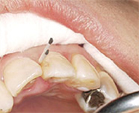

正常な骨の状態(根のまわりを白いモヤモヤ(骨)がおおっています)

骨が溶けてなくなっています(20代女性)(根のまわりが黒く、骨がありません)

なぜなら、レントゲンを撮れば骨が溶けているか、溶けていないかがわかります。

どこの骨が溶けているのか、溶けていないのか場所がわかります。

それがわかるのでどこの歯が重症か、悪化しているのかがわかるわけです。

どこの部分の歯周病菌の種類を調べてやればいいのか、わかるのです。

そこの歯周病菌の種類を調べてやれば大体、口の中は感染症だから原因の歯周病が何かわかるわけです。